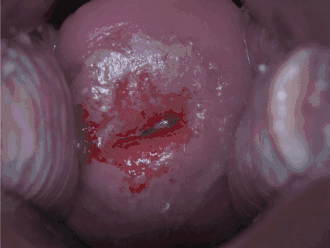

Diagnostic

Un test pour le HPV appelé le « test Digene HPV » est très précis et sert à la fois de diagnostic direct et d'adjuvant au frottis cervical. Une colposcopie avec biopsie dirigée est la norme pour la détection des maladies. Un prélèvement à la brosse endocervicale au moment du frottis cervical pour détecter l'adénocarcinome et ses précurseurs est nécessaire, ainsi que la vigilance du médecin/patient sur les symptômes abdominaux associés au carcinome utérin et ovarien. Le diagnostic de NCI ou de carcinome cervical nécessite une biopsie pour analyse histologique.[réf. nécessaire]

Dépistage

Les deux méthodes de dépistage disponibles sont le frottis cervical et le dépistage du VPH. La NCI est généralement découverte par un frottis. Le but de ce test est de détecter des changements potentiellement précancéreux grâce à un échantillonnage aléatoire de la zone de transformation. Les résultats du frottis peuvent être rapportés à l'aide du système Bethesda (voir ci-dessus). La sensibilité et la spécificité de ce test étaient variables dans une revue systématique portant sur l'exactitude du test. Un test de frottis anormal peut conduire à une recommandation de colposcopie du col de l'utérus, une procédure en cabinet au cours de laquelle le col de l'utérus est examiné sous grossissement à l'aide d'un microscope. Chaque zone d'apparence anormale fait l'objet d'un prélèvement/biopsie.[réf. nécessaire]

La colposcopie peut parfois être douloureuse chez certaines patientes. Certaines études suggèrent que l'injection d'un anesthésique local et d'un vasoconstricteur dans le col de l'utérus peut réduire la perte de sang et la douleur pendant la colposcopie[17].